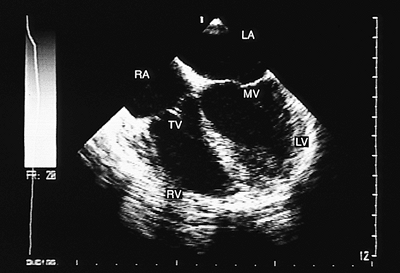

FIGURE 8.2.22. Concordant atrioventricular connection. The insertion of the tricuspid septal leaflet (TV) into the interventricular septum is more apical than the insertion of the mitral septal leaflet (MV). This information is useful in identifying the ventricles. LA, left atrium; LV, left ventricle; RA, right atrium; RV, right ventricle.

FIGURE 8.2.23. Concordant atrioventricular connection. The anatomically right ventricle (RV) can be identified by demonstrating the insertion of the tricuspid subvalvular apparatus (TV) into the interventricular septum. LA, left atrium; LV, left ventricle; MV, mitral valve; RA, right atrium.